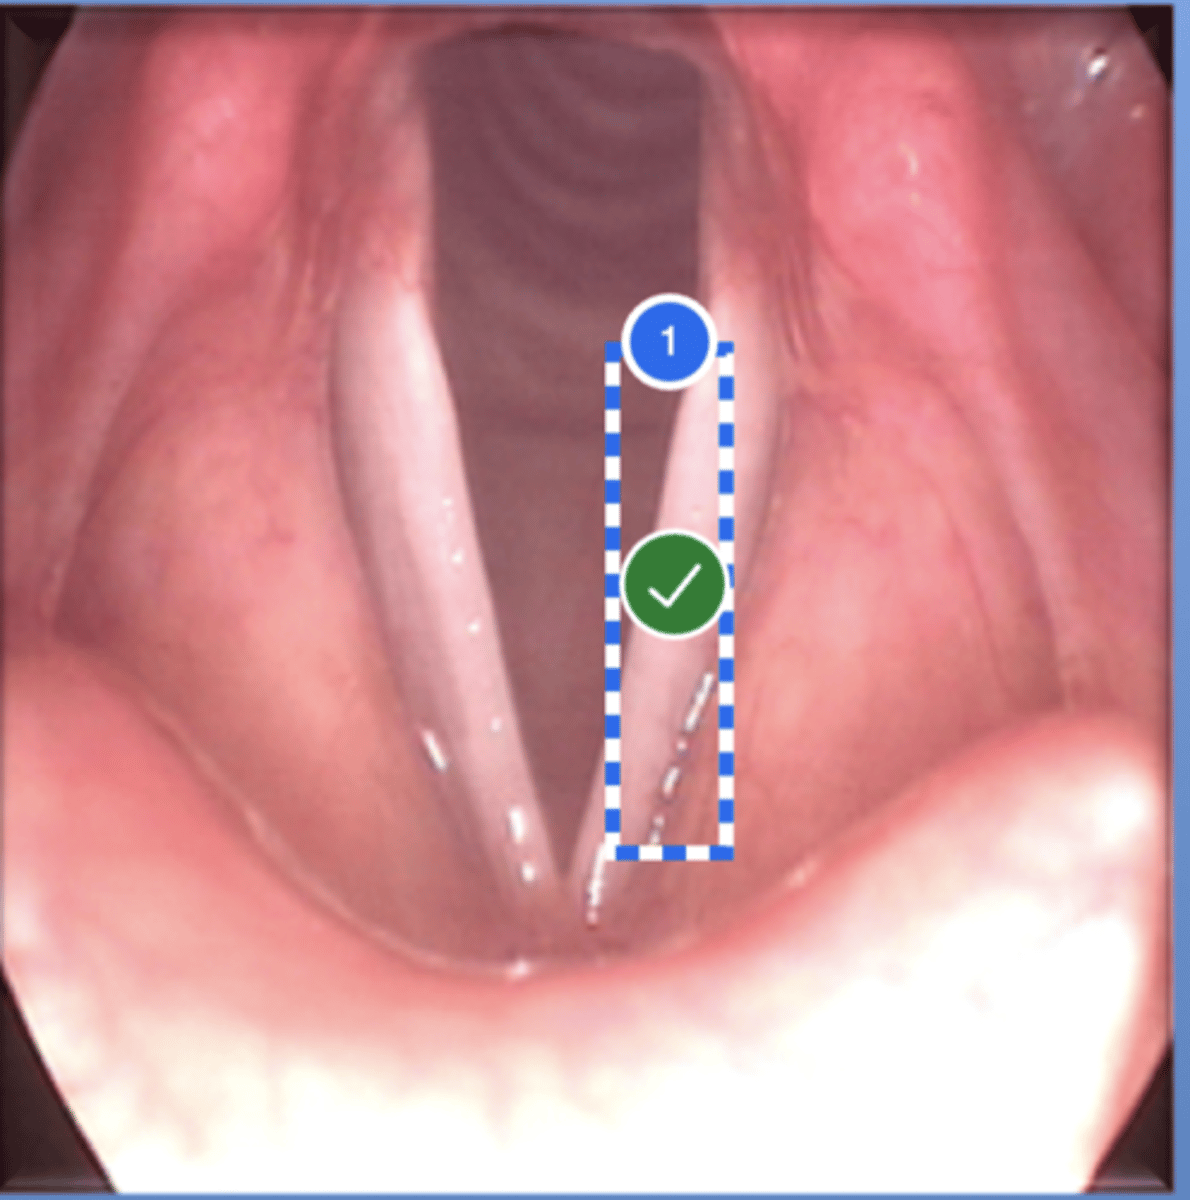

Label left true vocal fold (superior view)

Label right false vocal fold (superior view)

label right arytenoid (superior view)

Label trachea (superior view)

Label epiglottis (superior view)

Label right true vf (superior view)